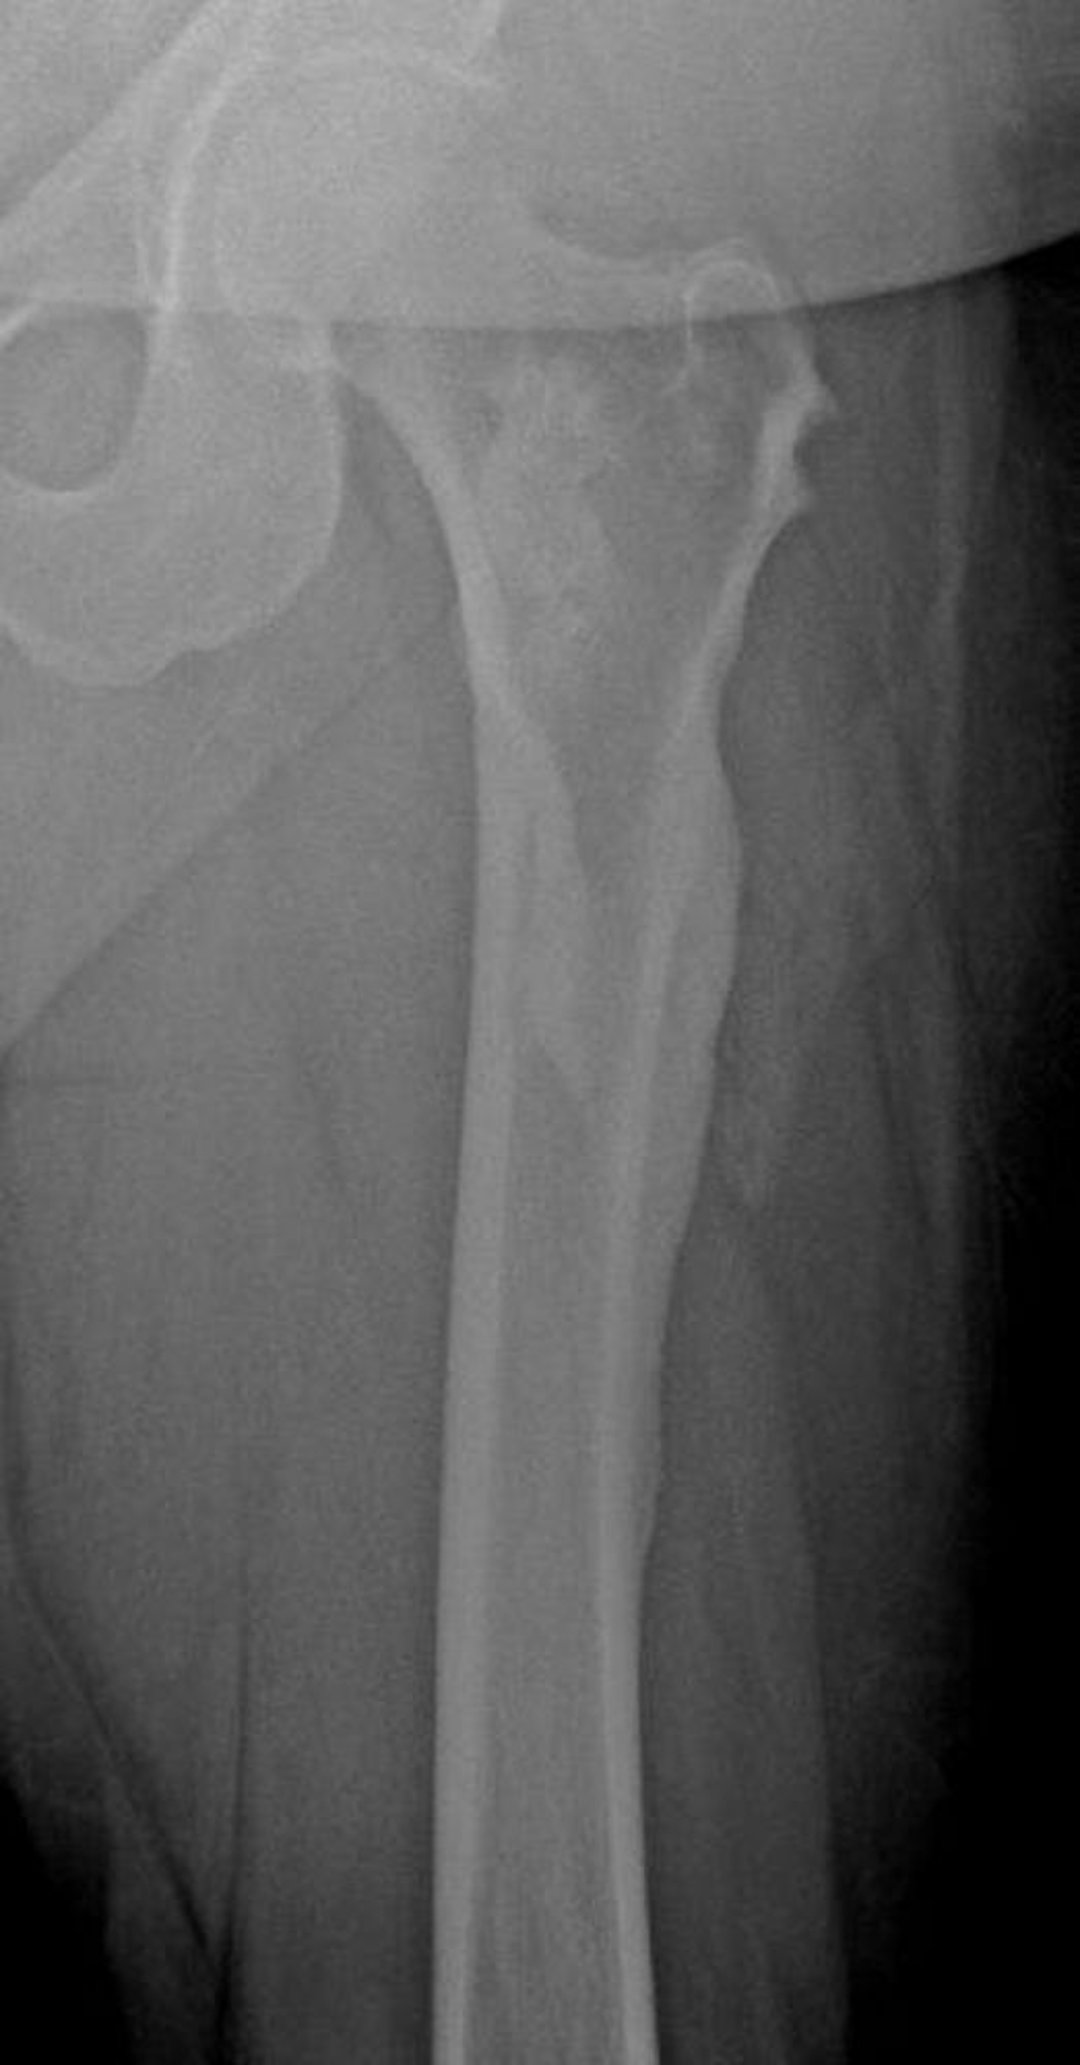

Melorreostose (cera derretida na margem de uma vela)

Esta radiografia evidencia a aparência de “cera de vela derretida” da melorreostose no fêmur, especialmente visível no córtex lateral do fêmur.

Imagem cedida por cortesia de Michael J. Joyce, MD, and David M. Joyce, MD.